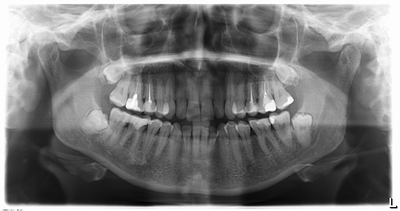

Удаление подобных зубов можно назвать более простым случаем по сравнению с другими, но только лишь в том случае, если у зуба один прямой корень. Тогда удаление может пройти достаточно быстро. Но такие клинические случаи встречаются крайне редко. И, посмотрев на снимок, мы видим крючья, а не корни, которые при должном давлении, могут просто сломаться. Корней обычно 2, и в таком случае нам просто нужно отделить один корень от другого при помощи все того же инструмента — «повышающего» наконечника . И аккуратно каждый из корней достать по отдельности. Начало и завершение удаления таких зубов такое же, как и у всех остальных.